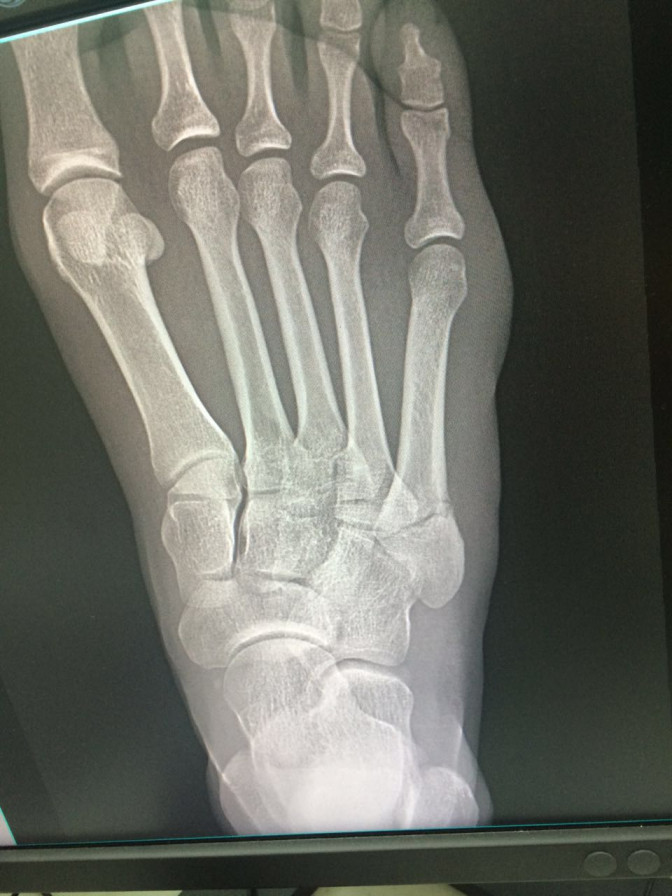

"Valoramos a Lina Flórez de atletismo por un trauma en su pie derecho ocasionado saltando una valla. Presenta clínicamente dolor al palpar la base del quinto metatarsiano. Incapacidad para el apoyo por dolor. Le tomamos rayos x que confirman el diagnóstico de fractura de quinto metatarso", confirmó Juan Carlos Quiceno, coordinador médico de la delegación colombiana en Rio.

El galeno agregó que "dada la imagen de la radiografía y la actividad de la atleta, consideramos que no debe competir y que se debe hacer cirugía con fijación temprana de la fractura, probablemente con un tornillo percutáneo, para favorecer la rehabilitación más rápida y el retorno más pronto al entrenamiento".